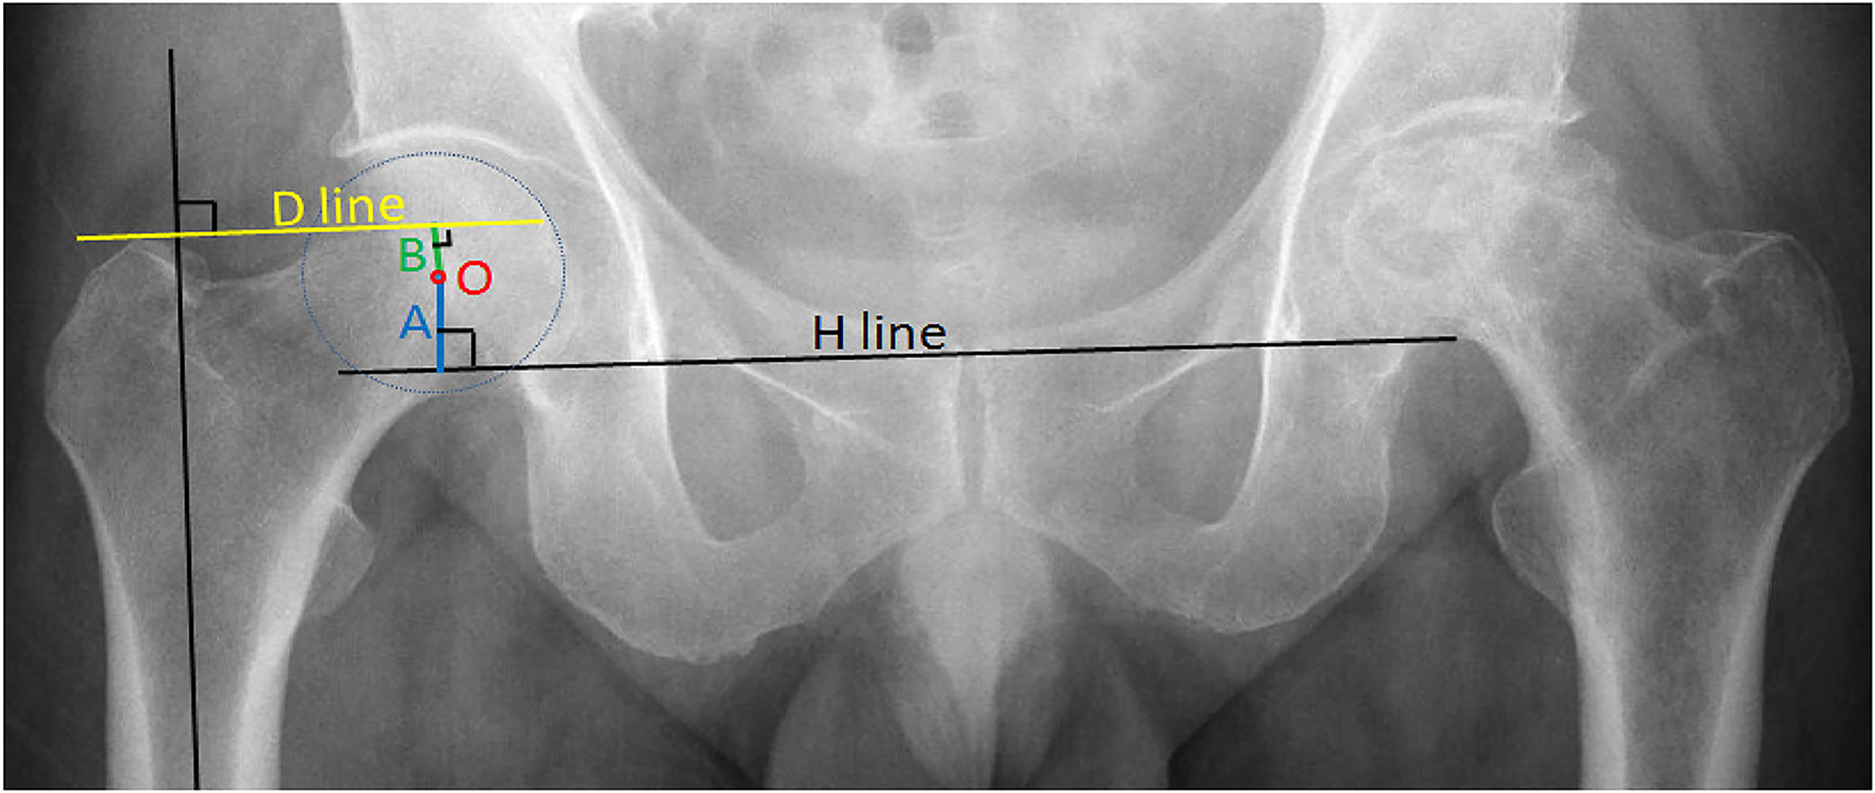

2.3.1. Measurement of the height of the acetabulum A

First, the H-line was drawn—the line through the lowest point of the two teardrops (the lower edge of the bony acetabulum)—and the rotation center (spot O) of the femoral head (it was also the center of the acetabulum) was found. Then, the distance from O to the H-line was measured, which was the acetabulum height A.

2.3.2. Measurement of the height of the femoral head B

Second, the D-line was drawn through the upper end of the great trochanter and vertical to the femoral longitudinal axis. Then, the distance from O to the D-line was measured, which was defined as the height of the femoral head B (if point O was above the D-line, a positive value was recorded; if point O was under the D-line, a negative value was recorded) (Figure 1).

Figure 1. Preoperative measurement of a healthy hip: A is the height of the acetabulum, and B is the height of the femoral head.